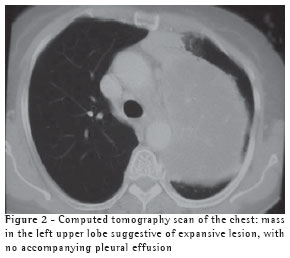

The computed tomography scan of the chest (Figure 2) confirmed the presence of a heterogeneous mass in the left upper lobe, with air bronchogram adjacent to the mass, suggesting an expansive neoplastic lesion. The patient was unable to produce a sputum sample for testing.

There is no characteristic radiological profile, although the presence of single or multiple nodules that are well defined and not calcified is more common and can mimic neoplasia on the X-ray.(5,9) Radiographic alterations have been reported, including infiltrates (62%), nodules (38%), masses (19%), cavitations (14%) and pleural effusion (3%), without anatomical distribution patterns and without any accompanying hilar or mediastinal lymph node enlargement. Empyema, pneumothorax and pleural involvement suggestive of Pancoast tumor,(13) as well as lung masses invading the chest wall,(14) have also been reported in the literature. A computed tomography scan of the chest corroborates the radiological findings, providing better details for the differential diagnosis,(11) and, when necessary, helps program the invasive diagnostic techniques. In the present case, the patient presented a lung mass that mimicked neoplasia.